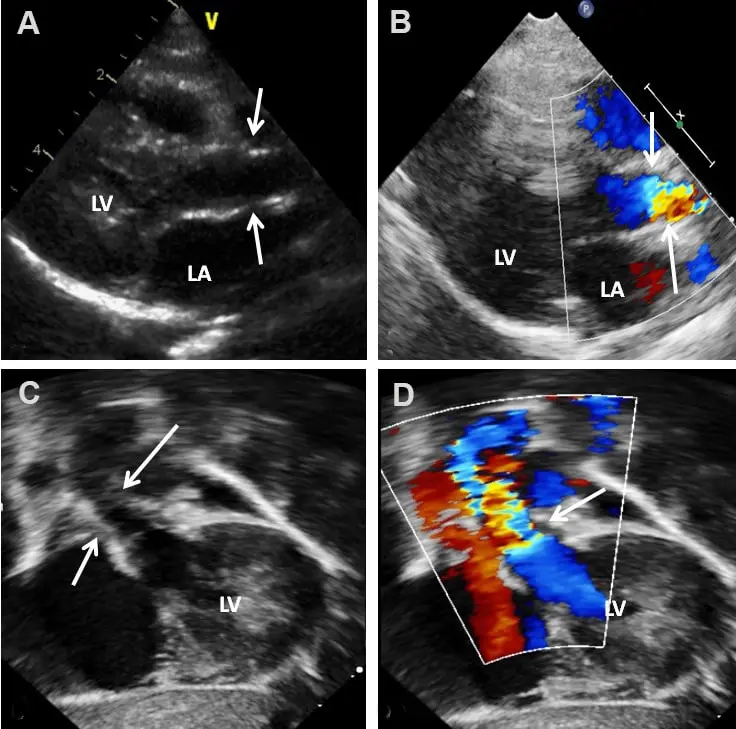

دکتر بهنام واقفی یکی از جراحان بسیار با تجربه در زمینه واریس و قلب می باشند که در کلینیک فوق تخصصی خود با استفاده از به روزترین و مجهزترین دستگاه ها و روش های نوین به درمان بیماران می پردازند.